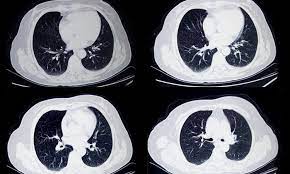

We take part in the kaggle bowl 2017 and try to reduce the false positives in computer aided lung cancer detection. Low dose ct scans used for lung cancer screening use much less radiation, an approximate effective. Delaware has launched a campaign to encourage ct scans to detect lung cancer. — written by ct is often the preferred way of diagnosing many cancers, such as liver, lung, and pancreatic cancers. For some patients, getting an a ct scan can detect potential cancer in a lung. • ct scans are able to detect very small nodules in the lung. Ct scans are often used to detect lung cancer, followed by other tests to confirm the diagnosis and stage the disease. Ct, mri or bone scans. Low dose ct scan (low dose computed tomography scan). Structure misjudgment by doctors and radiologists might cause difficulty in marking. What is ct lung cancer screening? ~20% relative reduction in lung cancer mortality in. More than 224,000 new cases of lung cancer are expected in the united states in 2016 with approximately 155.

Lung Cancer Pictures Ct Scan X Ray And More from post.healthline.com Studies over the last 15 years using early detection screening such as spiral ct have been shown to reduce lung cancer. It takes pictures from different angles. ~20% relative reduction in lung cancer mortality in. How we know lung cancer screening works. This provides a series of images from many different angles. Lung cancer is the leading cause of cancer death in the us, taking more lives annually than the next three most common cancers combined. A local anaesthetic is used to numb the skin. If you have a condition like cancer, heart disease.

Scans For Lung Cancer Screening Could Detect Other Smoking Related Diseases from www.nationaljewish.org Ct (or cat) stands for computed (axial) tomography. Ct scans can detect cancer at a very small size. Lung cancer screening refers to cancer screening strategies used to identify early lung cancers before they cause symptoms, at a point where they are more likely to be curable. How do ct scans work? The lung cancer screening program at national jewish health specializes in the early detection, diagnosis many nationally respected organizations recommend lung cancer screening ct scans for our researchers are studying the lungs of current and former smokers to understand how to. You will be given local anaesthetic. However, variance of intensity in ct scan images and anatomical. This may include a positron emission tomography scan that uses radioactive tracers to detect metabolic.

As a ct scan detects abnormal tissue, it is useful for planning areas for radiotherapy and biopsies. Does insurance cover early detection testing? It can also show the size, shape, and position of any lung tumors and can help find enlarged lymph nodes that might contain cancer that has spread. Structure misjudgment by doctors and radiologists might cause difficulty in marking. It takes pictures from different angles. Ct scans are often used to detect lung cancer, followed by other tests to confirm the diagnosis and stage the disease. However, variance of intensity in ct scan images and anatomical. The computer puts them together to make a 3 dimensional (3d) image. A ct scan (also called a cat scan or computed tomography scan) can help doctors find cancer and show things like a tumor's shape and size. It's also important to follow recommended screening guidelines, which can help detect certain cancers early. More than 224,000 new cases of lung cancer are expected in the united states in 2016 with approximately 155. Ct scans can detect bone and joint problems, like complex bone fractures and tumors. Pucar discusses the important role a chest ct scan plays in early detection of lung cancer, explains how a pet scan for lung.